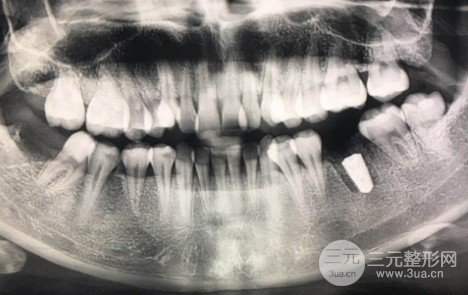

簡單說一下我的牙齒:今年20歲大二,高中時候因為緩解不積極(完全沒有及時就醫(yī))壞了??偸峭现辉敢鈸Q敷料導致緩解結束時牙齒很脆,然后因為吃東西而裂開。牙齒像中間的碗一樣碎了,不需要緩解,就在19年暑假拿出來了,拔完牙半年后去醫(yī)院了。種植牙的相關啊,也在網上學到很多理論知識,我去頭一家,這個大夫甚至跟我說還不錯。但是照完之后發(fā)現骨量不夠!我從來沒想過,因為骨量就像種樹里的土,我連土都不夠!經過三家醫(yī)院面對面診斷,結果是骨量不足,需要植骨,手術難度、風險、價格都上去了。當時整個下午還是很郁悶,為什么大家都正常做了,我還要去做額外的一次手術?但每個人自身情況不同,術前面診和計劃尤為重要,于是去了同濟口腔醫(yī)院。